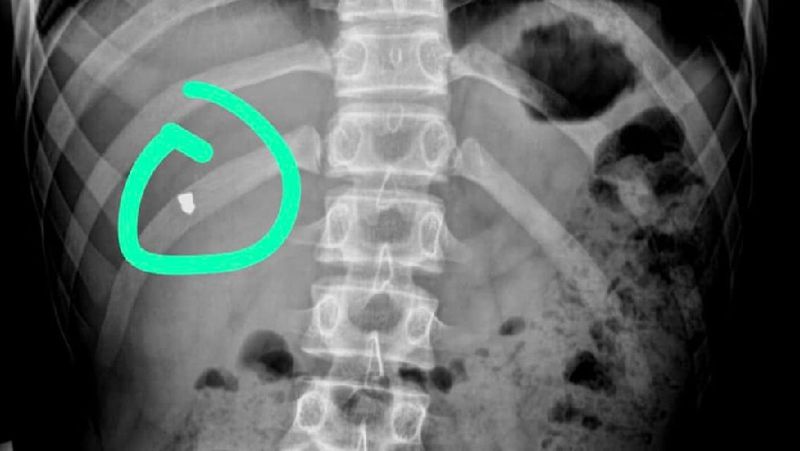

В Мангистау врачи вытащили пулю из грудной клетки подростка